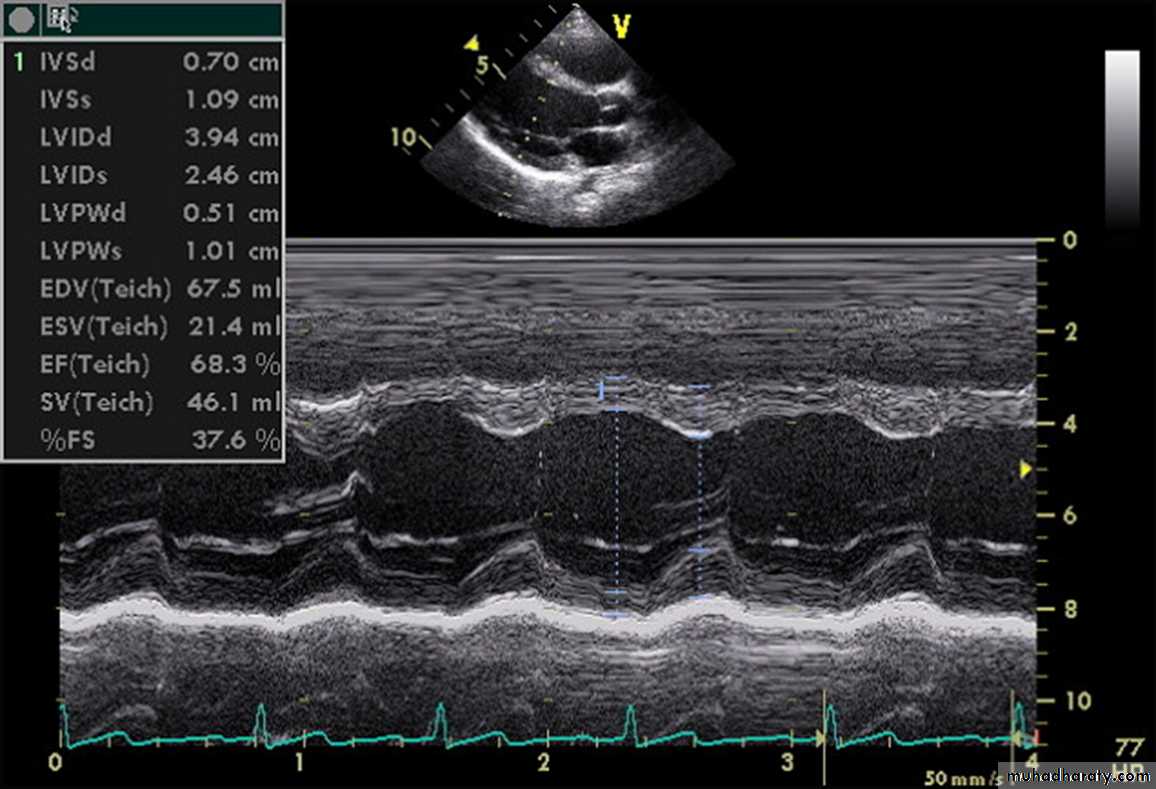

Echo studies may confirm enlargement of ventricular chambers and impaired LV systolic function (low fractional shortening or ejection fraction) as well as impaired diastolic function by the use of Doppler techniques.

A more important role of echo may be due to its ability to determine the cause of CHF.

Echo is also helpful in serial evaluation of the efficacy of therapy.